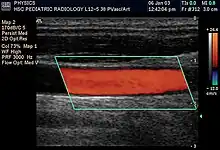

Doppler ultrasonography is used to study blood flow and muscle motion. The different detected speeds are represented in color for ease of interpretation, for example leaky heart valves: the leak shows up as a flash of unique color. Colors may alternatively be used to represent the amplitudes of the received echoes.

Doppler ultrasonography

Doppler ultrasonography employs the Doppler effect to assess whether structures (usually blood)[52][54] are moving towards or away from the probe, and their relative velocity. By calculating the frequency shift of a particular sample volume, flow in an artery or a jet of blood flow over a heart valve, its speed and direction can be determined and visualized, as an example. Color Doppler is the measurement of velocity by color scale. Color Doppler images are generally combined with gray scale (B-mode) images to display duplex ultrasonography images.[55] Uses include: